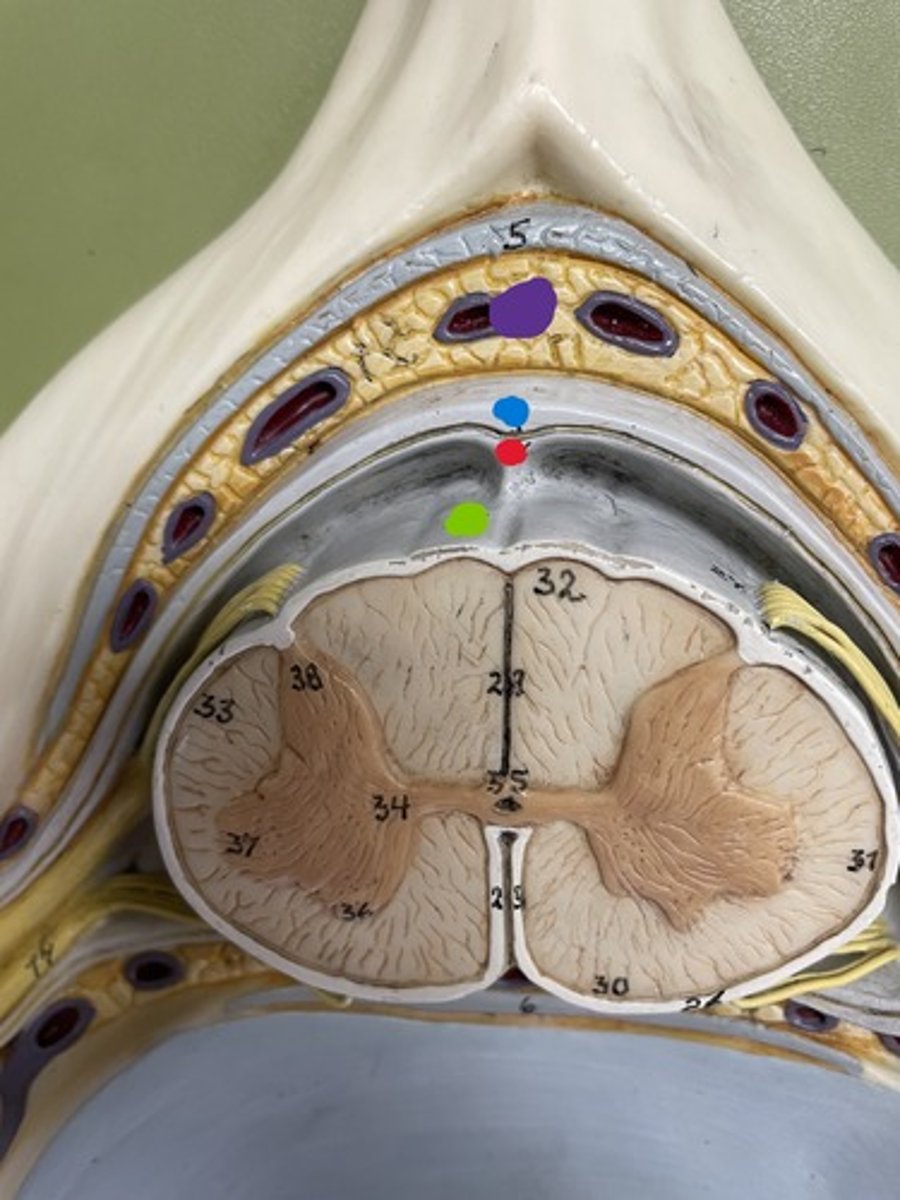

Cervical enlargement

Blue

Lumbar enlargement

Purple

Conus medullaris

Green

Gray matter

Posterior horn

Anterior horn

Lateral horn

G

Gray commissure

gray matter around this structure

Central canal

White matter

Posterior funiculus

Green

Anterior funiculus

Yellow

Lateral funiculus

Red

Posterior median sulcus

green

Anterior median fissure

red

Dura mater

blue

Arachnoid mater

red

Pia mater

green

Epidural space

purple

Subdural space

between red and blue

Subarachnoid space

between red and green